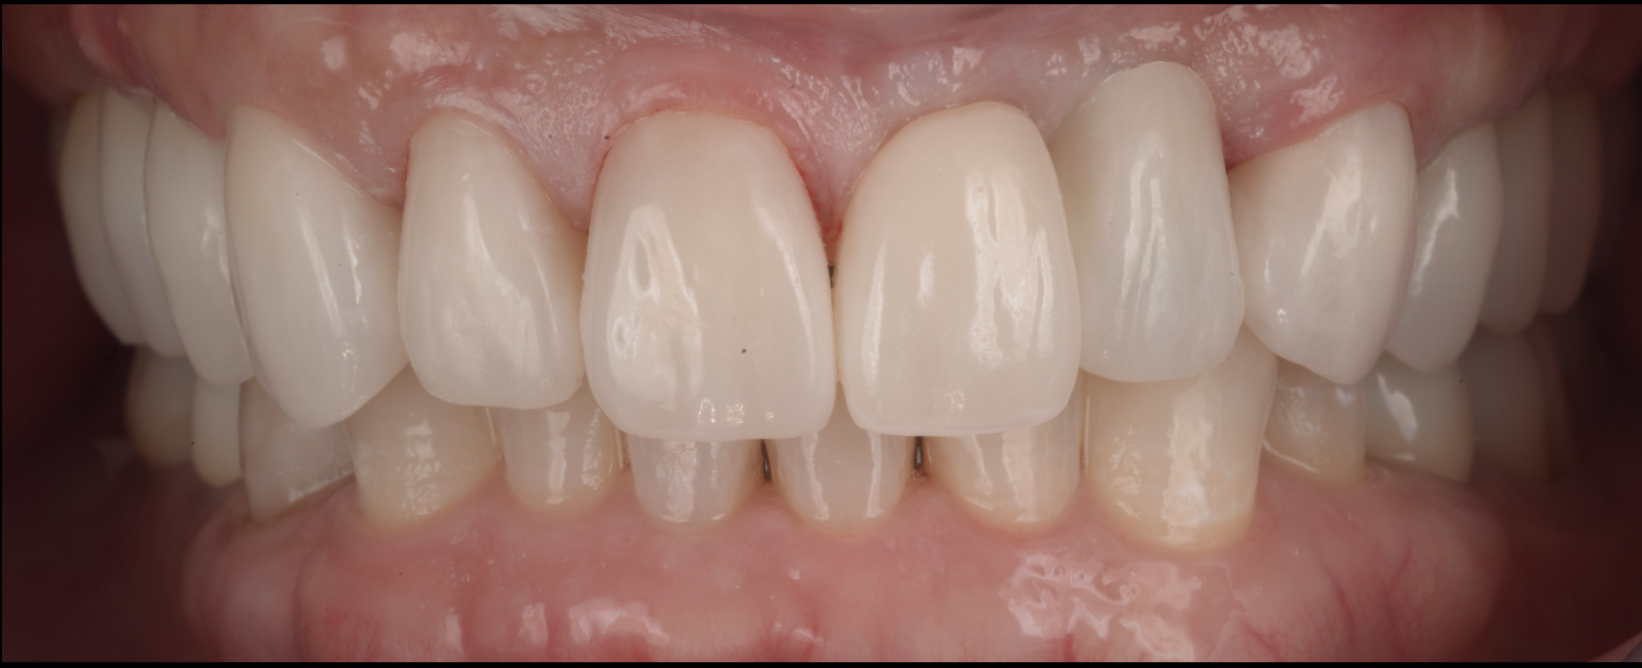

上唇の腫脹を認め、CT検査にて根尖部に嚢胞様透過像を認めた。左上の前歯が不自然に大きく噛み合わせが強くなっていたことがフレアアップの一因と考える。精密根管治療を行い、感染経路を遮断したのち歯根端切除術にて嚢胞を摘出した。

治療後

| 治療内容 | 精密根管治療、歯根端切除術、セラミック修復 |

歯の保存、嚢胞の摘出、審美的改善